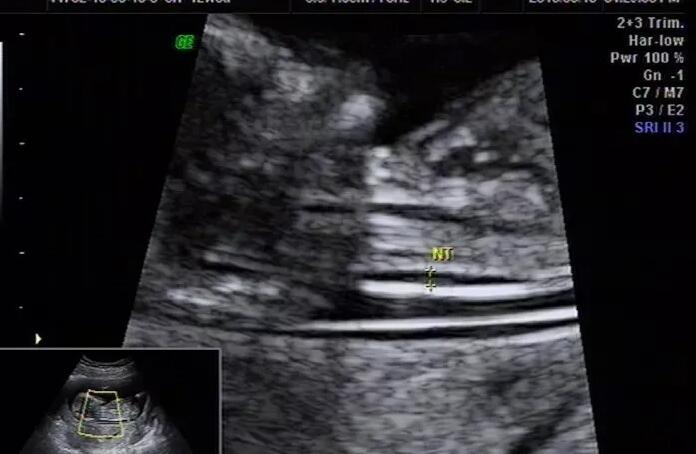

3.在促排卵期间,要通过B超、检测性激素等手段来判断卵泡的大小、成熟度,确定取卵的时间,B超、抽血时应不会有太大的痛苦,这是女性经常做的检查;